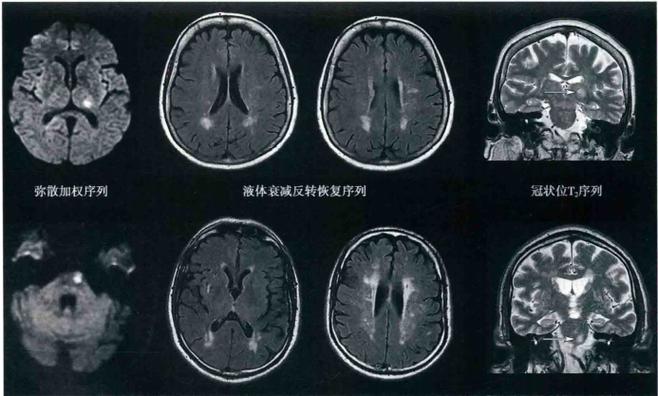

- 影像学检查证实病灶稳定:通过复查头颅CT或MRI(磁共振),可以看到梗塞的病灶已经“陈旧化”,周围的水肿已经完全消失,形成了一个小的软化灶,这个病灶会永久存在,但它已经不再“活跃”,不会继续扩大或产生新的损害。